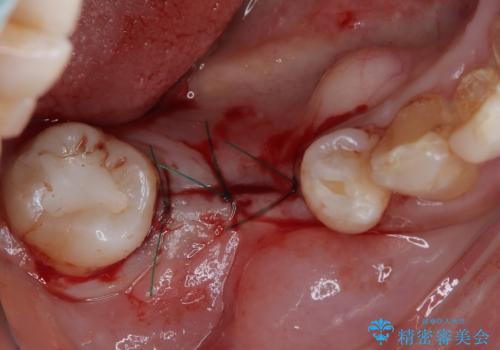

- 以前根管治療を行った歯が痛むとのことで来院された患者様です。

レントゲン写真より、歯根周辺に大きな病変(炎症により骨が溶けている状態)が認められたため、歯根が破折している可能性が示唆されました。

歯根が破折した歯は抜歯となるため、抜歯して病変の部分に骨が回復するのを待って、インプラントによる補綴治療を行うこととしました。

病変が大きかったことや、神経や血管が多く通る管が近いこともあり、抜歯即時埋入ではなく、骨の治癒が待ってから埋入を行う、従来の方法にてインプラント治療を行いました。